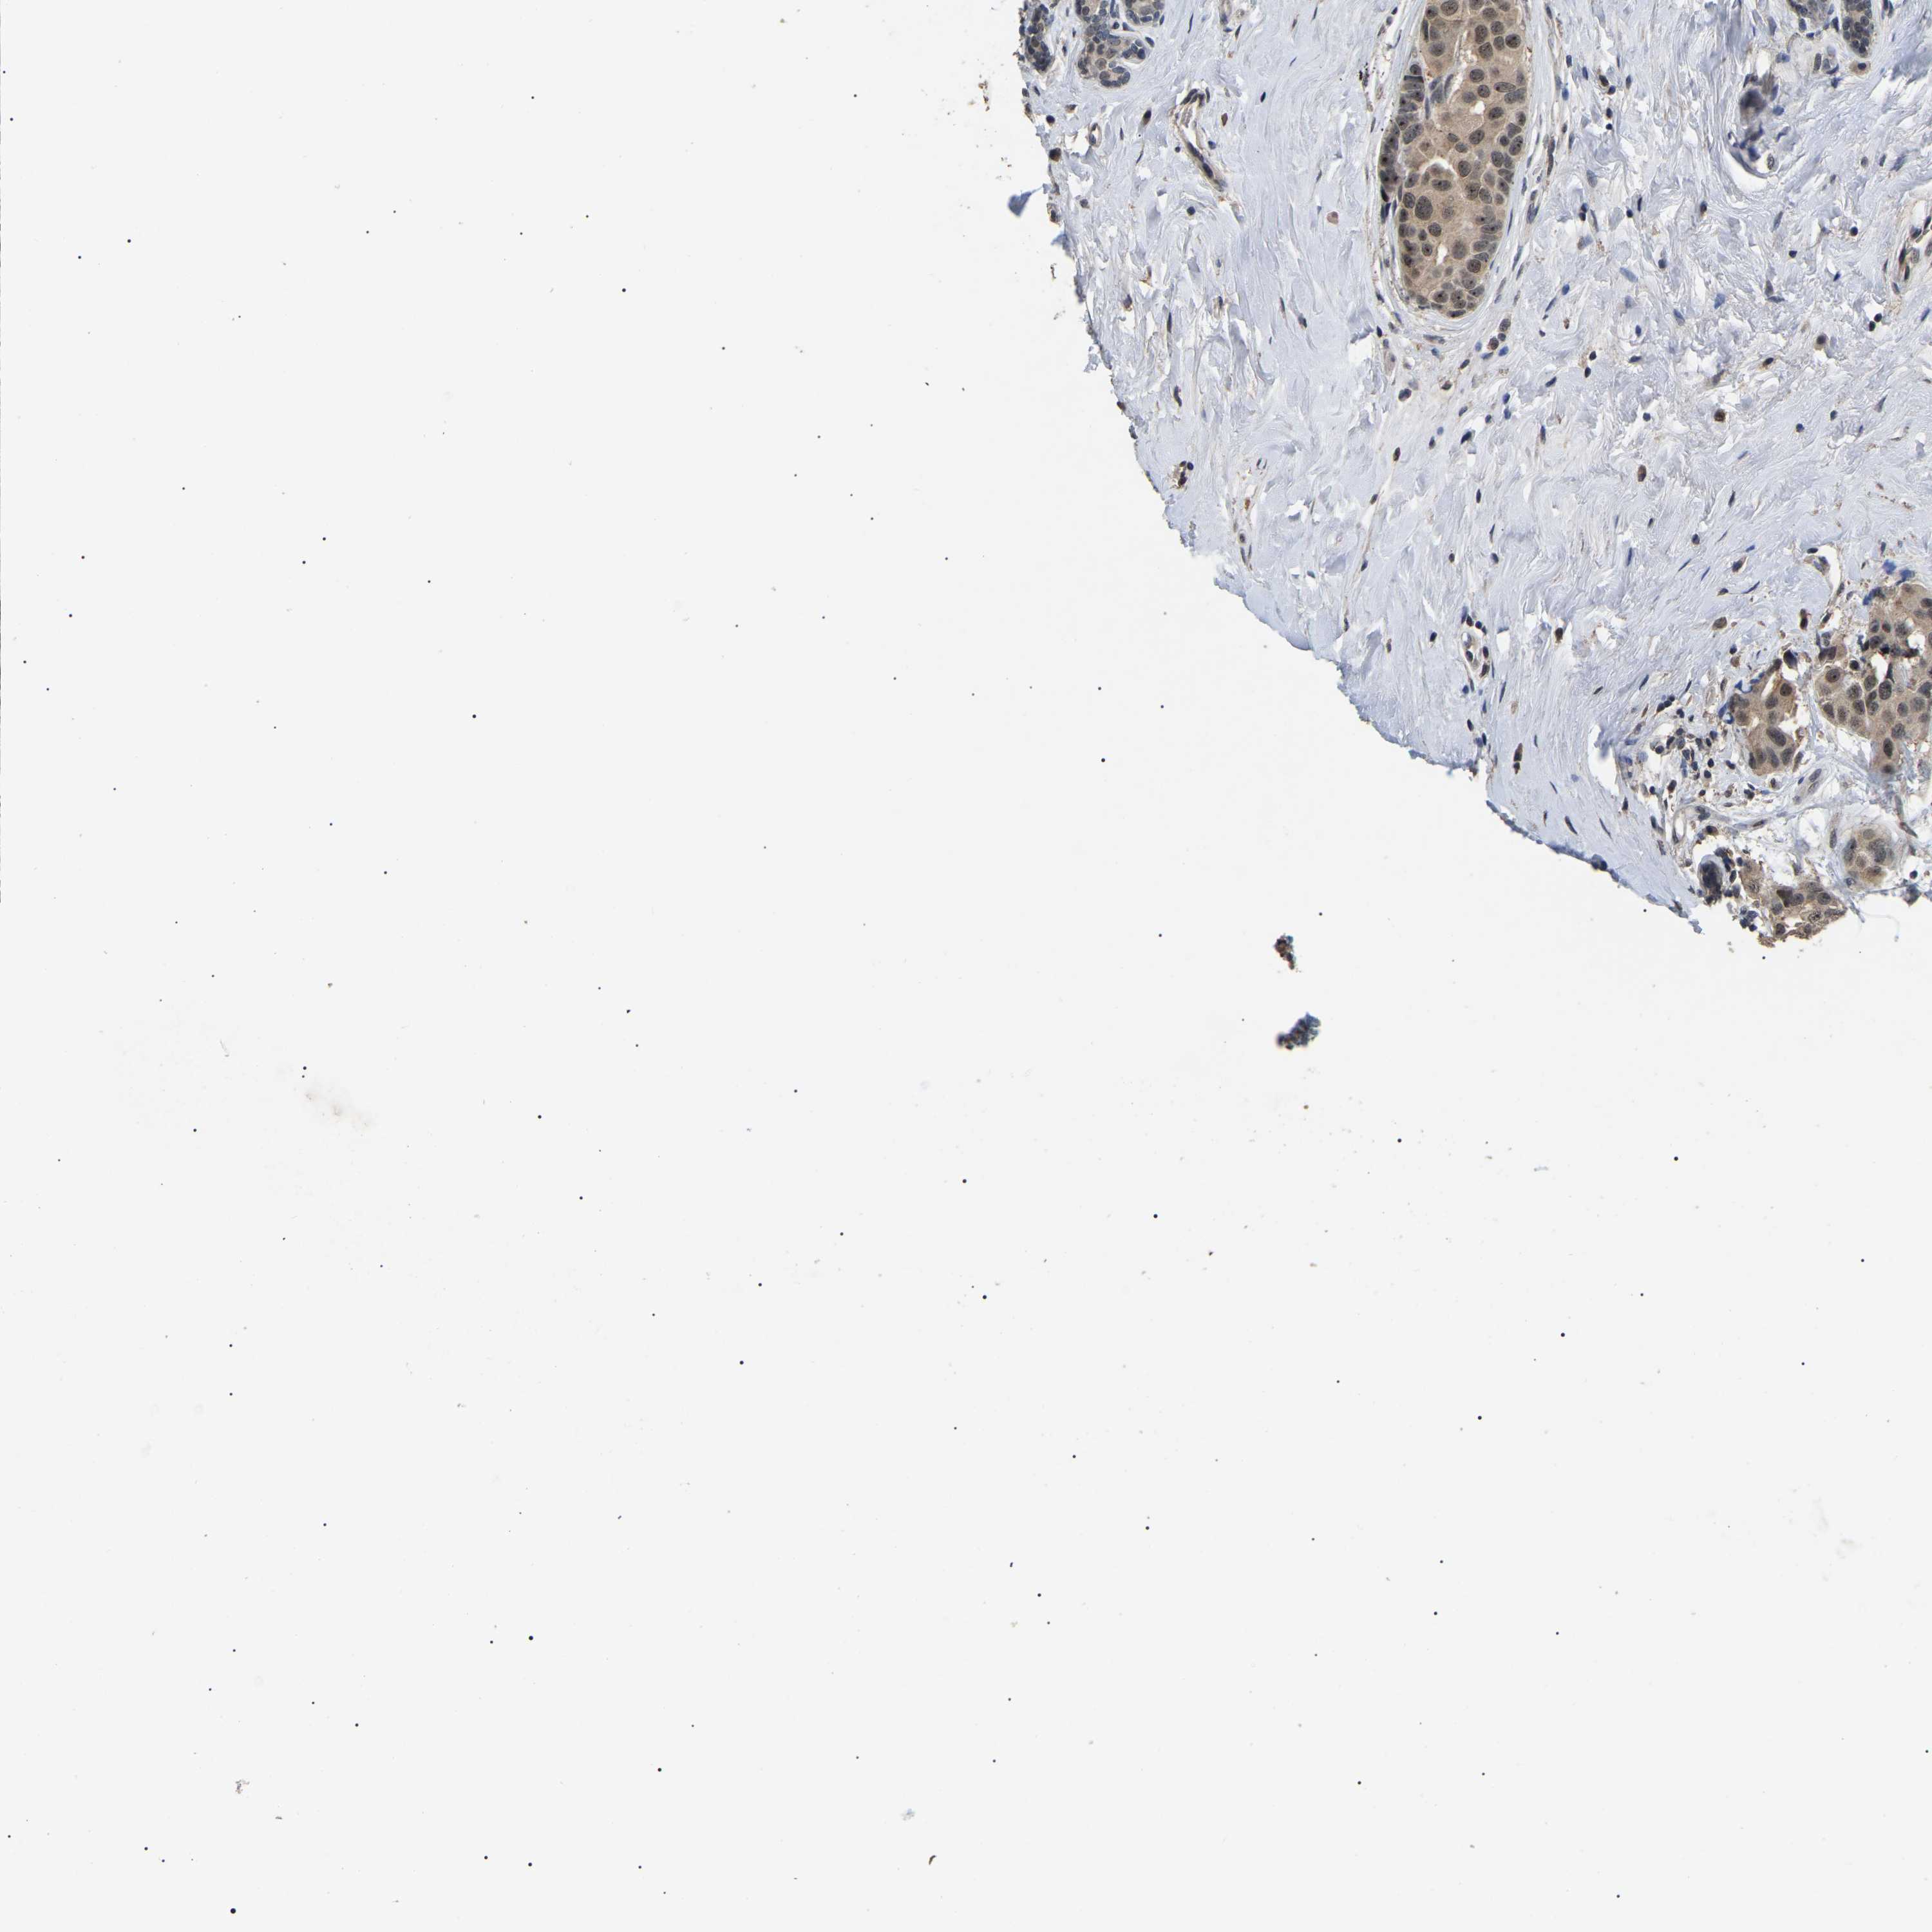

CANCER BREAST CANCER Show tissue menu

BRCA TCGA BRCA VALIDATION PROTEIN EXPRESSION